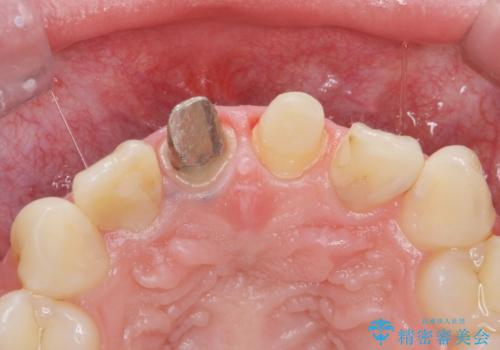

- 前歯のバランスが悪いとの事で来院。

左の前歯は樹脂での治療がされていてう蝕が再発していたので全て取り除き、再根管治療(保険)を行いました。

右の前歯も被せ物を外して左右一緒に作製した方が同じ色で作れるので被せ物のやりかえを行いました。(再根管治療は望まなかった)

根管治療をした後、樹脂で埋めるだけで治療を終えてしまうと歯質と樹脂の隙間から細菌が入り込み、う蝕や根の感染の再発に繋がります。

適合の良い被せ物を入れることで再発リスクが低くなります。